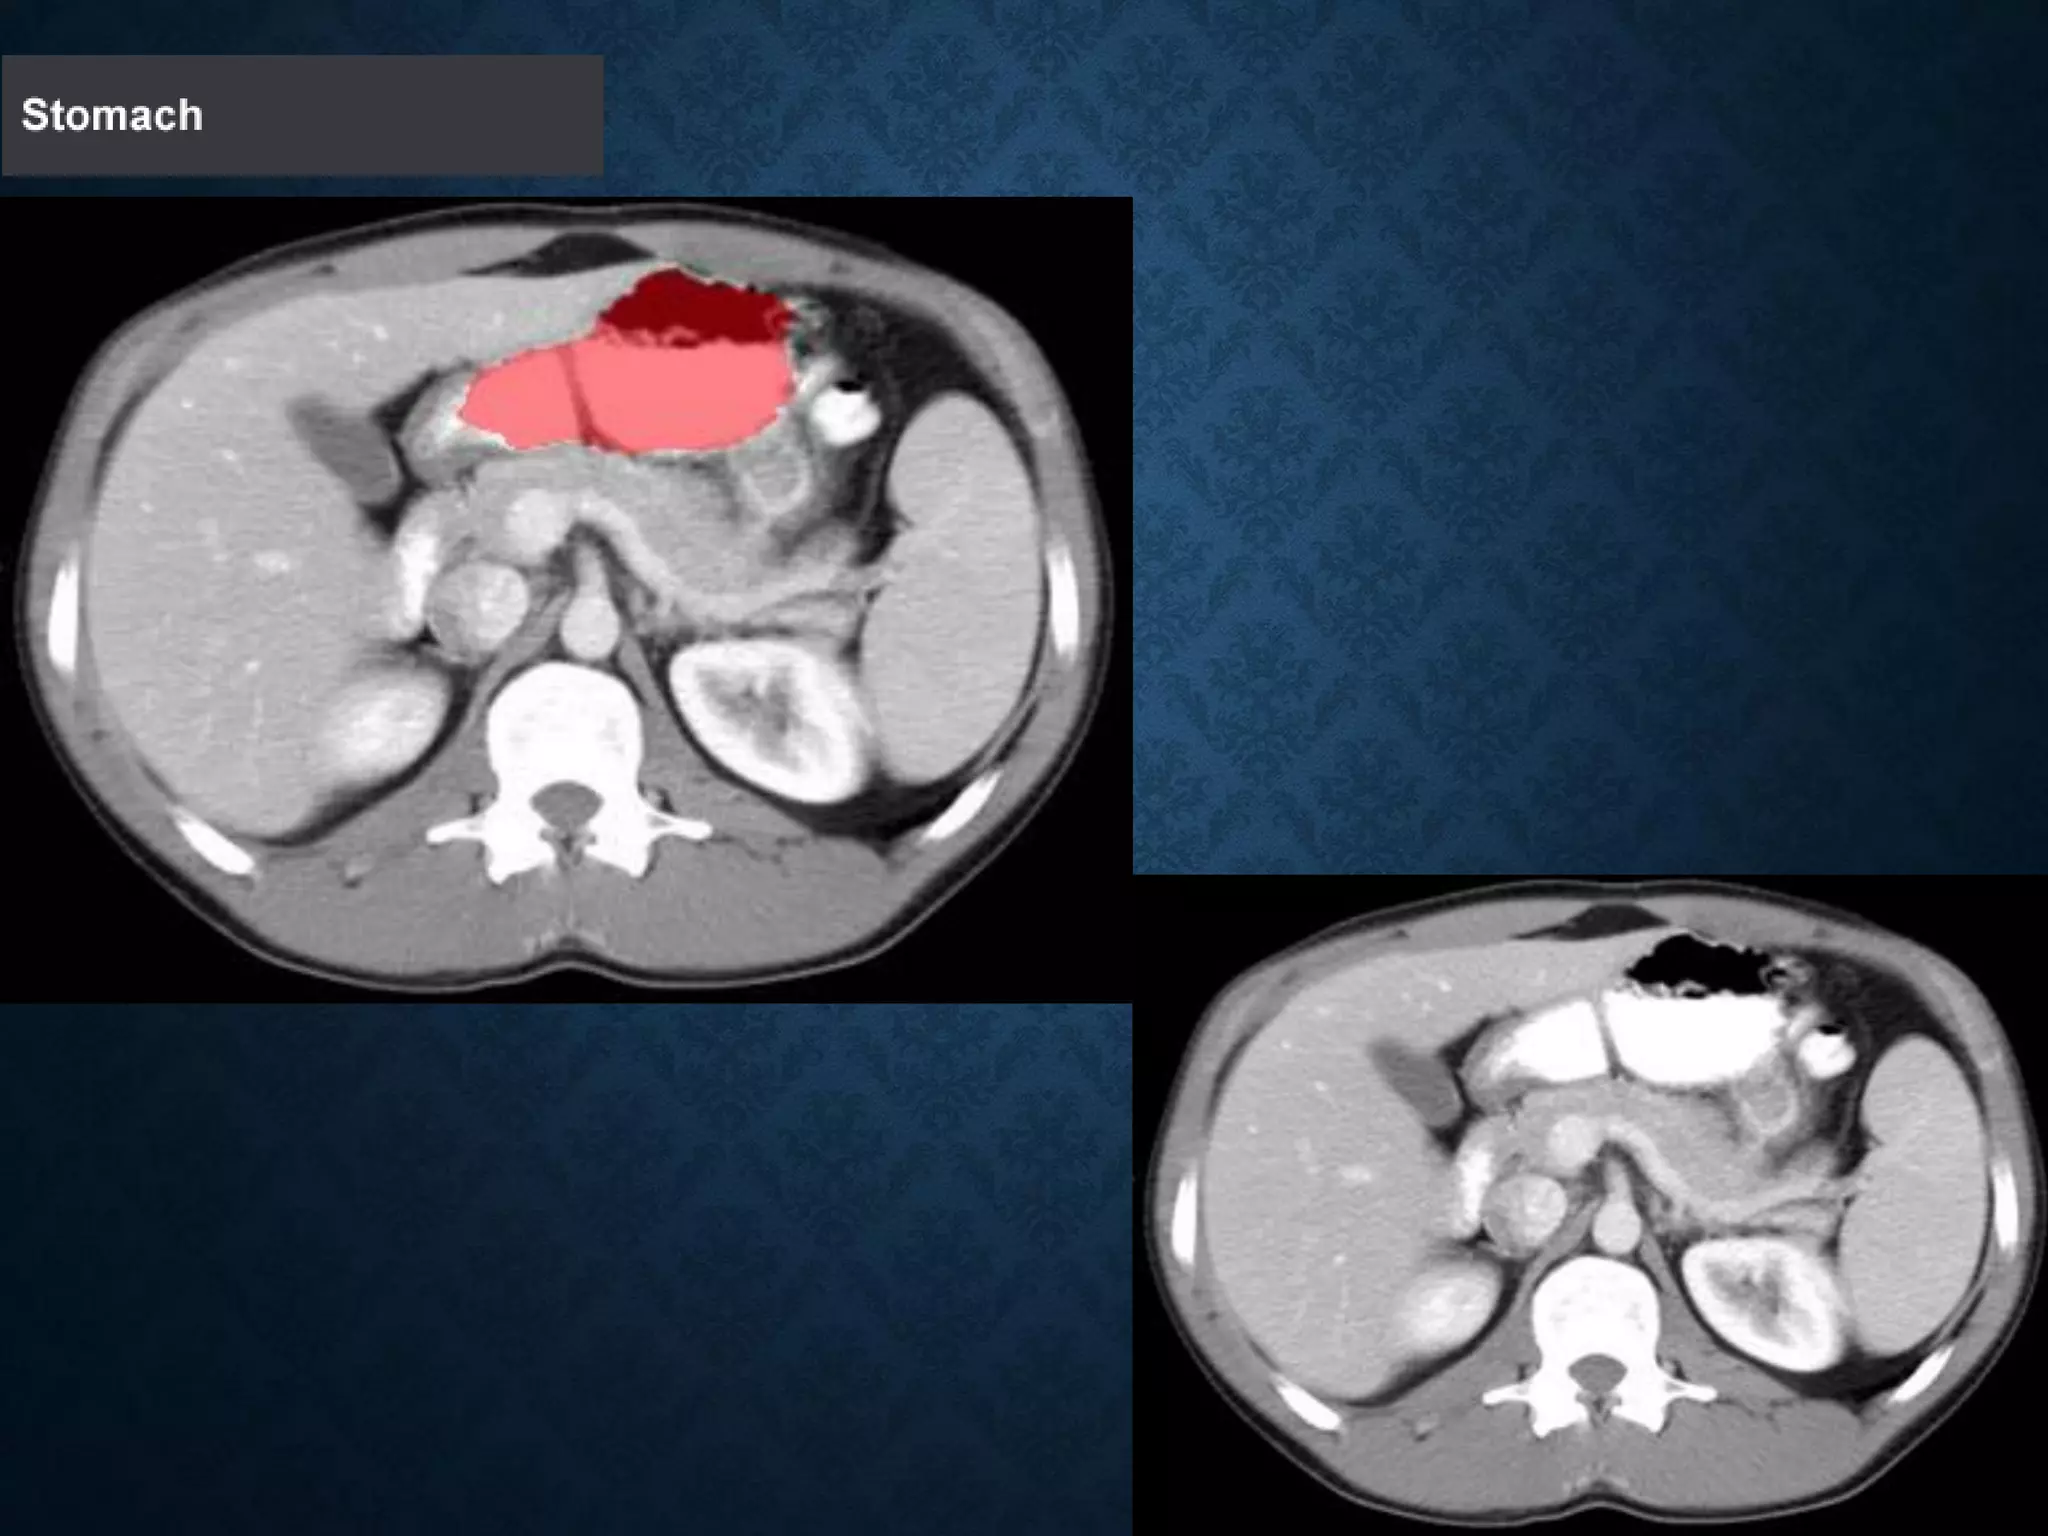

STOMACH